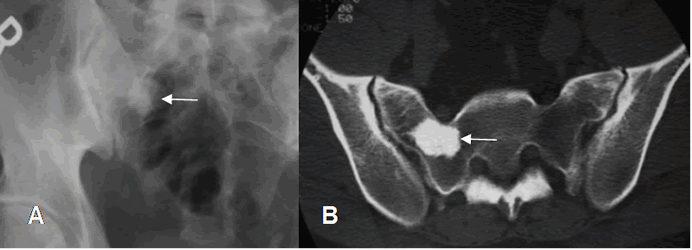

Fig 51. Enostosis.

A: Rx AP. Lesión espiculada y densa en la región intertrocantérica, que corresponde a enostosis.

Fig 52. Enostosis.

A: Rx AP y B: TAC axial. Imagen densa y espiculada en el alerón del sacro derecho,

por enostosis.